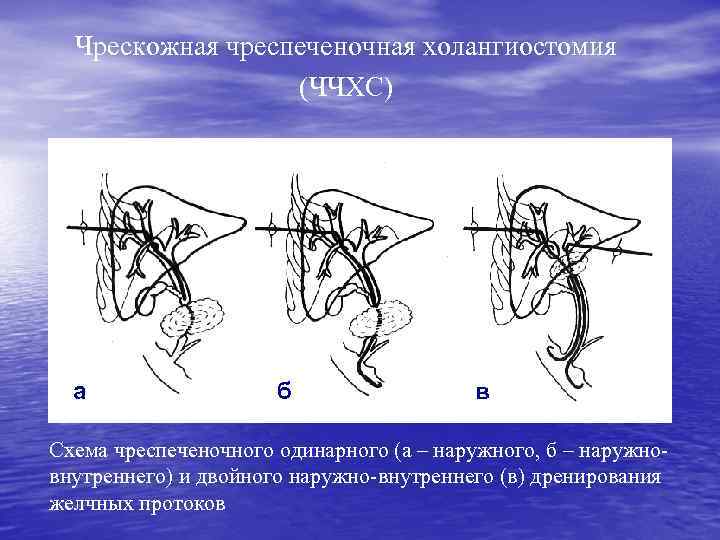

Чрескожная чреспеченочная холангиостомия (ЧЧХС) а а б б в в Схема чреспеченочного одинарного (а – наружного, б – наружновнутреннего) и двойного наружно-внутреннего (в) дренирования желчных протоков